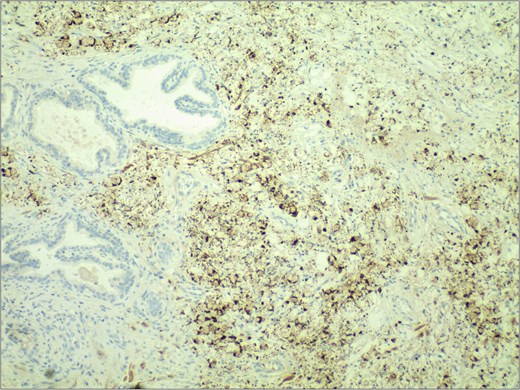

In November 2024, the patient presented with progressive dysuria for 3 years, accompanied by recurrent urinary retention for 3 weeks. Physical examination revealed a prostate enlarged to grade II, with a firm texture, smooth surface, no palpable nodules, no tenderness, a shallow median sulcus, and no sphincter relaxation. Imaging studies with 3.0 T prostate magnetic resonance imaging (MRI) showed a prostate measuring ⁓5.7 × 4.8 × 5.7 cm, with marked enlargement of the transition zone and heterogeneous signals. Small, patchy short T2 signals were internally observed, along with slightly high diffusion-weighted imaging (DWI) signals and slightly decreased apparent diffusion coefficient (ADC) signals, yielding a PI-RADS score of 3. The peripheral zone was thinned and indistinct. The seminal vesicles showed normal size and morphology, and the bladder-seminal vesicle triangle was intact. No enlarged lymph nodes were evident in the pelvic cavity. Laboratory tests showed a total prostate-specific antigen level of 1.759 ng/ml. Initially diagnosed with benign prostatic hyperplasia, the patient underwent transurethral enucleation of the prostate with a thulium laser under general anesthesia on 19 November 2024. The surgery was successful. Postoperative pathology indicated poorly differentiated adenocarcinoma, predominantly signet ring cell carcinoma, presumed to be of gastric origin (Fig. 1). Immunohistochemical analysis revealed negativity for prostate cancer markers (PSA and P504S) and positivity for gastrointestinal tumor markers [CKP(3+), CK20(+), CEA(3+), Villin(2+), CDX-2(2+)] (Fig. 2). Morphological comparison with previous gastric cancer pathology slides showed similar features, confirming metastatic gastric signet ring cell carcinoma to the prostate. The patient continued chemotherapy with the original gastric cancer regimen postoperatively and is currently under follow-up.

Immunohistochemical staining demonstrated strong positivity (++) for villin in the cytoplasm and cell membrane of tumor cells. IHC stain 40×.